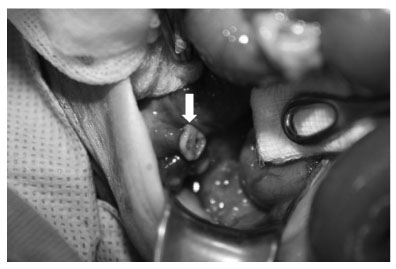

Fig. 2

Abdominal exploration shows the appendix completely transected (arrow).

Fig. 2 Abdominal exploration shows the appendix completely transected (arrow).